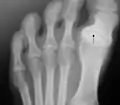

Hallux varus

"Hallux varus is a clinical condition characterized by medial deviation of the great toe at the metatarsophalangeal joint. [abbreviation excised]".[1] This condition when acquired by adults is usually caused by sports injury, surgical overcorrection of hallux valgus, or underlying causes such as arthritides.[1]